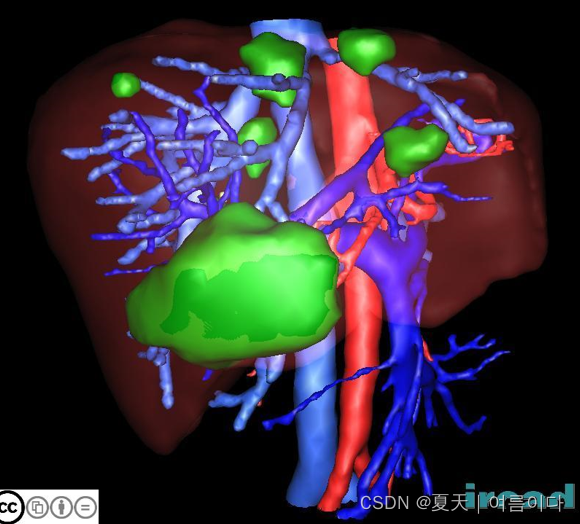

2.1.3D-ircadb-01

3D-IRCADb-01 数据库由 10 名女性和 10 名男性 75% 的肝肿瘤患者的 3D CT 扫描组成。 20个文件夹对应20个不同的患者,可以单独下载也可以联合下载。下表提供了图像信息,例如肝脏大小(宽度、深度、高度)或根据 Couninaud 分割的肿瘤位置。它还表明肝脏分割软件可能遇到的主要困难是由于与邻近器官的接触、肝脏的非典型形状或密度,甚至图像中的伪影。

这些文件夹被称为“ 3D-IRCADb-1- number ”( 数字 在 01 和 20 之间变化)。这些文件夹被称为“ 3D-IRCADb- 01- number ”( 数字 在 01 和 20 之间变化)。每个“ 3D-IRCADb-01- number ”文件夹包含 4 个子文件夹,分别称为“ PATIENT_DICOM ”、“ LABELLED_DICOM ”、“ MASKS_DICOM ”和“ MESHES_VTK ””。这些文件夹分别包含 DICOM 格式的匿名患者图像、对应于 DICOM 格式分割的各个感兴趣区域的标记图像、一组新的子文件夹,这些子文件夹对应于包含 DICOM 图像的各个分割感兴趣区域的名称每个掩码,最后是与 VTK 格式的各个感兴趣区域的表面网格对应的所有文件。

论文地址:http://www-sop.inria.fr/geometrica/events/wam/abstract-ircad.pdf

数据集下载地址:Liver segmentation – 3D-ircadb-01 - IRCAD